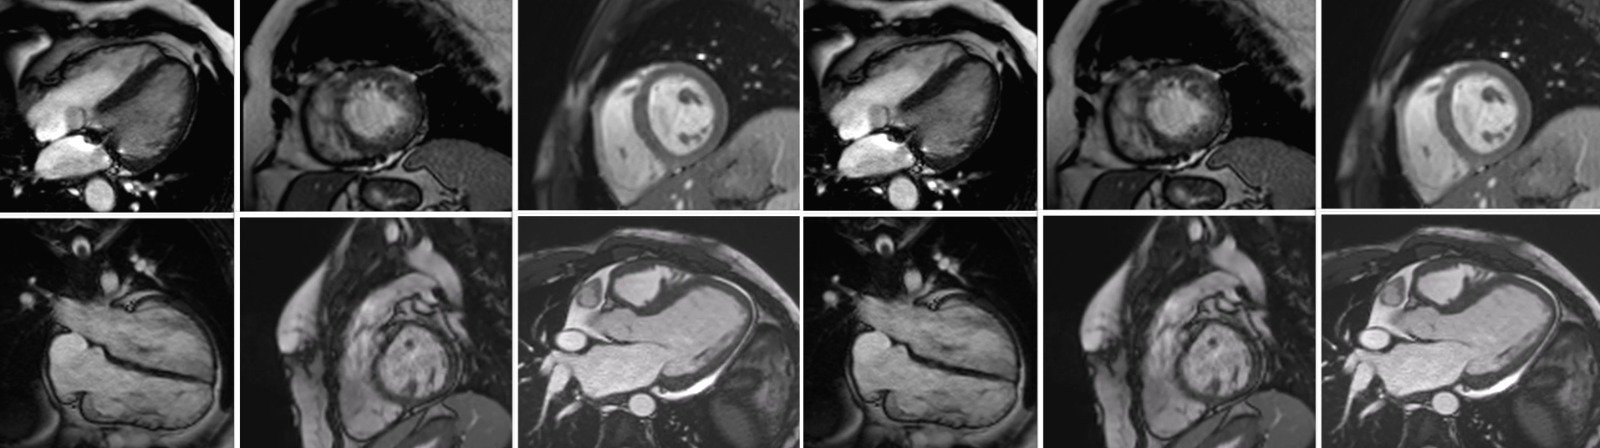

Rezonanța magnetică cardiovasculară (Cardio-RM) este cea mai avansată metodă imagistică de evaluare a funcției inimii. La Emerald, investigația este realizată de o echipă formată dintr-un medic radiolog cu experiență și un medic cardiolog specializat în RM cardiovasculară, în timpul acesteia fiind preluate peste 1500 de imagini de pe inimă, cu ajutorul unui aparat de ultimă generație, mai rapid, mai precis și mai silențios. Rezonanţa magnetică este o scanare nedureroasă și inofensivă, ce permite să privim în interiorul corpului fără utilizarea razelor X. Cu ajutorul unui magnet şi a undelor radio obţinem imagini detaliate, de foarte bună calitate cu privire la structura şi funcţia inimii.

Centrul Medical Emerald se află în acest proces de certificare europeană de peste 8 luni de zile, existând o listă foarte strictă de criterii, de la echipamentele tehnice și software folosite la acreditările echipei medicale, numărul de investigații realizate și chiar tipurile de secvențe utilizate, fiind obligatorii o înaltă calitate a examinărilor și acoperirea unei arii mari de patologii, incluzând patologii congenitale, cardiomiopatii, miocardită sau boală cardiacă ischemică.